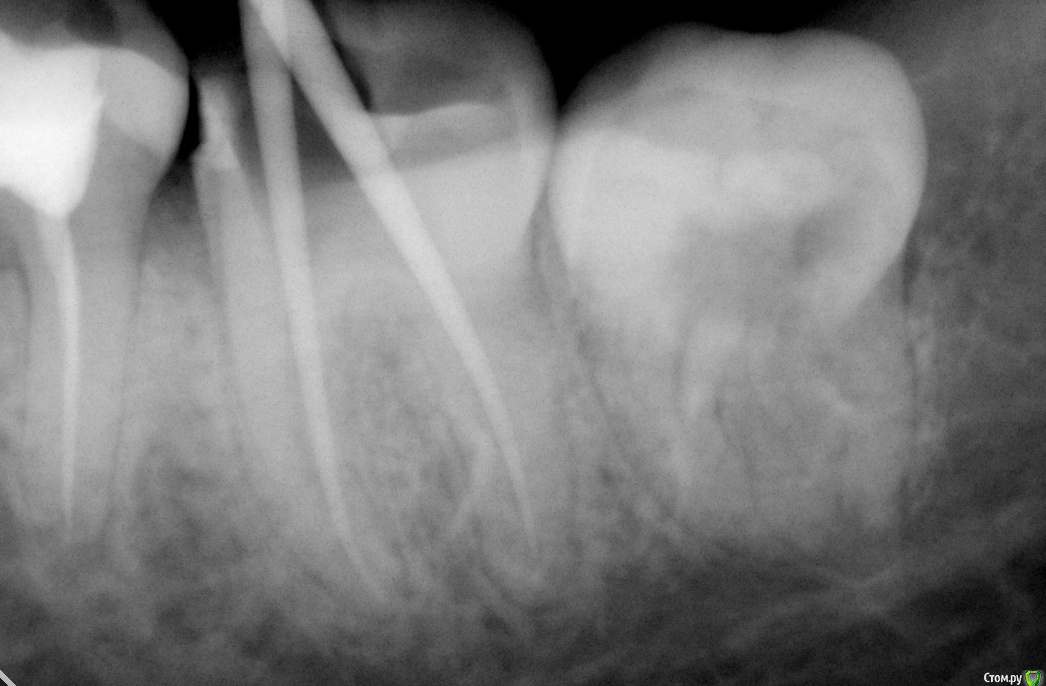

Jea Опубликовано 24 декабря, 2015 Поделиться Опубликовано 24 декабря, 2015 Добрый день! Помогите разобраться в сложившейся ситуации. Очень нужна оценка проведенного лечения сторонним экспертом. Хронология событий: 07.11 - первичный прием. Жалобы: ноющая боль в 7м левом нижнем зубе, носящая периодический характер, усиливающаяся в ночное время. Реакции на горячее/холодное, кислое/сладкое не было. Установленный диагноз: пульпит. Проведенные манипуляции: удаление нервов. 14.11- Пломбировка каналов. 21.11 - установка постоянной пломбы. 20.12 - повторное обращение по проведенному раннее лечению. Жалобы: боль после лечения не проходящая в течении месяца (нояющая, усиливающаяся в ночное время, при надкусывании). Есть левой стороной я не могла. Диагноз: воспалительный процесс в зубе. Манипуляции: распломбировка каналов, закладка лекарства, временная пломба. В течение 2х дней сильные постпломбировочные боли. Вечером 22.12 опухла десна. 23.12 прием по осложнениям после лечения, в ходе которого выяснилось, что во время распломбировки каналов зуб треснул и внесенное в канал лекарство вылилось в десну. Предложенный план лечения: удаление+ имплантация. Необходима оценка качества проведенного лечения и прогноз на дальнейшее лечение зуба. Прикрепляю все снимки, сделанные в ходе лечения. Благодарю! Ссылка на комментарий

Jea Опубликовано 24 декабря, 2015 Автор Поделиться Опубликовано 24 декабря, 2015 Мне надо понять, зуб треснул в результате некачественного лечения? А также действительно ли он треснул (видно ли это на снимках)? Необходима ли была распломбировка каналов? КАк вообще были запломбированы каналы? Ссылка на комментарий

St. Опубликовано 24 декабря, 2015 Поделиться Опубликовано 24 декабря, 2015 А также действительно ли он треснул (видно ли это на снимках)? Да, похоже на то. Ссылка на комментарий